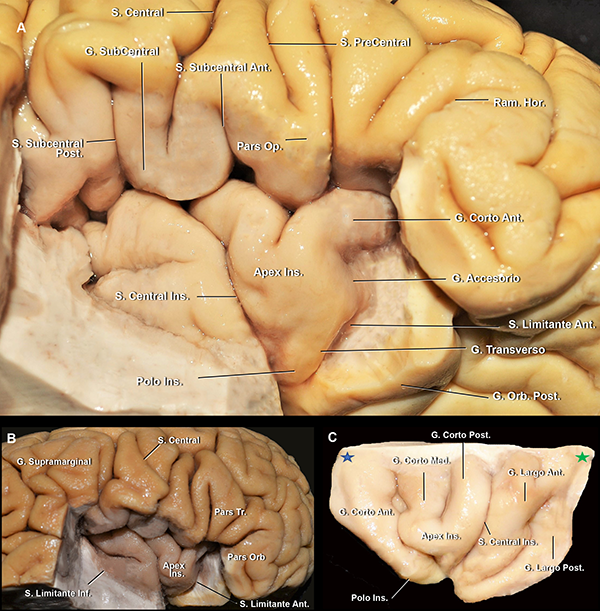

El tronco silviano se extiende hasta la punta inferior de la pars triangularis. En dicho vértice, se originan los tres ramos. Este punto es conocido como punto silviano anterior (Figura 3).

Los ramos de la FS son: 1) el ramo horizontal, 2) el ramo ascendente y 3) el ramo posterior, que cursa entre la parte posterior del opérculo frontoparietal y el temporal, y usualmente finaliza como una bifurcación en el giro supramarginal: el ramo ascendente terminal y el ramo descendente terminal. Este último, suele ser más corto que el anterior y es inconstante. El punto silviano posterior está ubicado en el extremo distal del ramo posterior, en el punto donde los ramos terminales se originan (Figura 3). Se describen dos ramos adicionales que se originan en el ramo posterior: el surco subcentral anterior y posterior (Figura 4A). Estos dos surcos se localizan anterior y posterior al surco central, respectivamente. Por detrás del punto silviano anterior, se encuentra el punto rolándico inferior (Figura 3). El punto rolándico inferior es definido como el punto de encuentro entre el surco central y la FS. Sin embargo, en el 70% de los casos de nuestra serie, el surco rolándico no se intersectó directamente con la FS en la superficie lateral del cerebro. Consecuentemente, el punto rolándico inferior también se refiere al punto de intersección de la proyección del surco central con la FS.

Figura 3: Vista lateral de un hemisferio cerebral derecho. Estrella azul: punto silviano anterior. El limen insular, el genu de la ACM y, frecuentemente, la bifurcación de la ACM se localiza medial e inmediatamente anterior a este punto. Estrella naranja: punto rolándico inferior. Estrella roja: punto silviano posterior. La ínsula se proyecta lateralmente desde el ramo horizontal a la parte más anterior del giro supramarginal; y desde la parte más superior de la pars triangularis y el ramo ascendente hasta el surco temporal superior. Línea punteada verde, azul y roja: proyección de los surcos semicirculares insulares anterior, superior e inferior, respectivamente. S: surco; G: giro; Ram: ramo; Sup: superior; Med: medio; Asc: ascendente; Desc: descendente; Term: terminal; Orb: orbitalis, Tri: triangularis; Op: opercularis; Hor: horizontal.

Figura 4: A. Vista latero inferior de un opérculo frontoparietal derecho. El opérculo temporal, la parte lateral del giro orbitario posterior y la parte posterior del giro orbitario lateral fueron removidas. Cuando el surco central no alcanza a la FS, el giro subcentral es visible en la cara lateral cerebral. En cambio, cuando sí lo hace, como en este caso, este giro se localiza en la profundidad de la fisura. Se observa cómo el ramo horizontal se continúa medialmente con el surco limitante anterior. El ápex insular se localiza superior y posteriormente al polo insular. B. Vista lateral del mismo espécimen. C. Vista de la superficie lateral de la ínsula de otro espécimen. Estrella azul: punto insular anterior. Estrella verde: punto insular posterior. S: surco; G: giro; Ant: anterior; Post: posterior; Op: opercularis; Ram: ramo; Hor: horizontal; Orb: orbitario; Ins: insular

Figura 5: A. Vista lateral de un hemisferio cerebral izquierdo. B. RMN, secuencia T1, corte sagital. La pars triangularis tiene forma de “V” (líneas rojas). Luego, encontramos 3 giro con forma de “U” (flechas azules), de anterior a posterior: 1) pars opercularis; 2) giro subcentral; y 3) la conexión entre los giros postcentral y supramarginal. Finalmente, la flecha verde marca la conexión con forma de “C” entre los giros supramarginal y temporal superior. Se observa al giro de Heschl enfrentado al postcentral. Ambos se encuentran en el mismo plano coronal que el CAE. Asterisco: proyección medial del CAE. S: surco; G: giro; Sup: superior; inf: inferior.